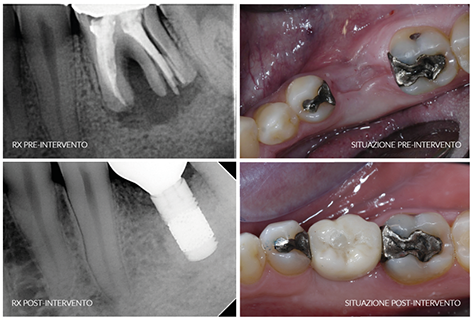

Die Studie, „Knochentransplantation und ohne Primarstabilität sofort eingefügte Implantate: neue Operationstechnik“ weist auf konkreter Weise nach, dass ein Trabecular MetalTM Implantat – durch eine besondere, aus Tantal ausgezeichnete poröse Struktur, welche mit der Substantia spongiosa vergleichbar ist und den Nachwuchs der Knochen, sowie dessen Integration mit dem Metall, fördert – eine perfekte Osseointegration ermöglicht, auch mangels der Primärstabilität (ohne dass der Implantat an den Knochen angeschraubt wird). Voraussetzung für die Erzielung eines guten Ergebnisses, ist dass dieses Implantat sofort nach der Extraktion eines Zahnes eingefügt wird, zugleich mit einem homologen (menschlichen) Knochen als Stütze. Unter Osseointegration versteht man eine starke und dauerhafte Bindung zwischen Knochen und Metall.